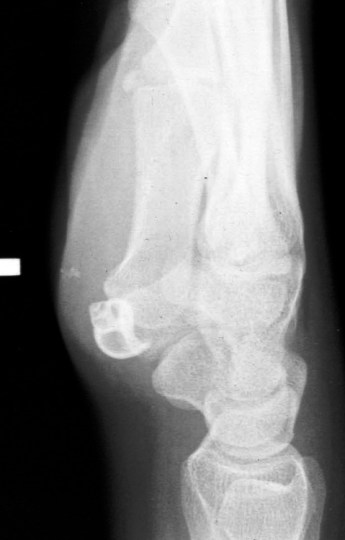

- If you hit the reef hard the pain may distract you from sprains and joint damage. Be suspicious of pain in the joints either side of the injury.

- Remember its possible to damage nerves and arteries beneath wounds.

- If the coral cut is deep and potentially entering a joint space you should go to a hospital for surgical cleaning.